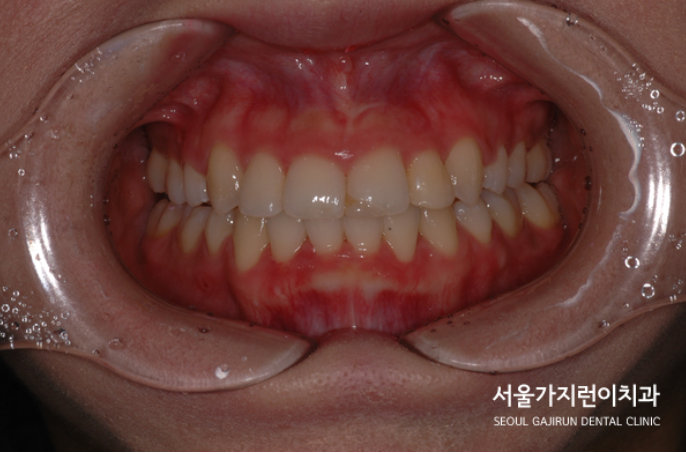

원하는만큼의 돌출감 해소는 물론이고 치아의 뿌리까지 이동이 용이하기 때문에 안정성이 확보되는 교정방법. 위의 기술로 환자분의 심한 덧니 교정은 진행이 되었으며 치아배열과 뻐드러짐, 돌출의 정도를 함께 개선해나갔습니다.

그리고 이게 치료 30개월이 지난 정면 사진입니다. 앞서 보였던 심한 덧니의 모습은 온데간데 없죠. 교정 전부터 완료시점까지 사진을 찍어 남겨두기 때문에 환자분의 케이스가 많은 분들에게 용기를 주었으면 좋겠습니다. 저희 서울가지런이치과 교정과 의원에서는 교정을 전문적으로 진행하는 곳으로 복잡해보이는 심한 덧니 증상도 충분히 개선하고 있는데요. 수많은 임상경험을 통해 안정성이 입증된 장비만을 사용하고 있으니 더 자세한 내용이 필요하시면 하단의 배너를 참조해 주시기 바랍니다.